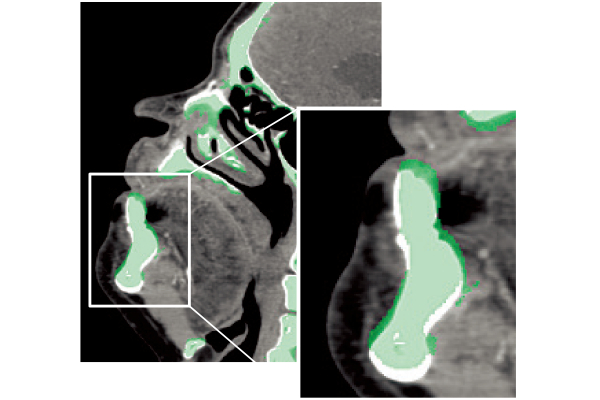

The captured scanogram image can be used to automatically set the scan range. This can be expected to be shorten the setting time. By using Fujifilm's automatic organ segmentation technology*7, which was developed utilizing deep learning, it contributes to the scan of a total of 14 types, including the head and chest. In addition, since the margin of the scan area can be set in advance, the scan area can be customized according to the operation of each facility. The operator can also check and adjust the automatically calculated scan area.

REiLI makes it happen to extract organs and simplify your work.

Kidney